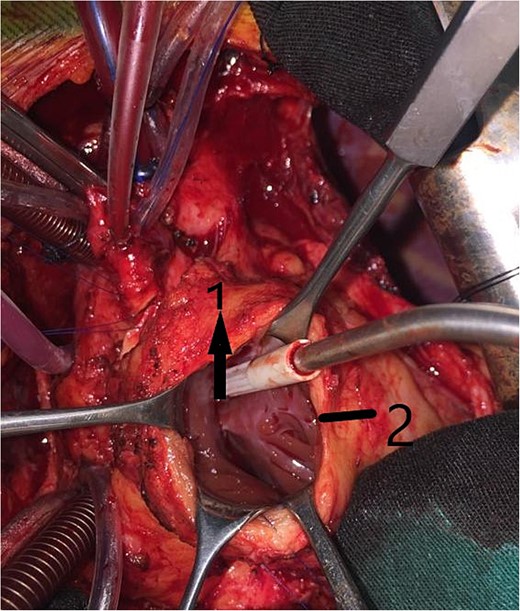

An 11-year-old girl was referred to our hospital with a main complaint of progressive exertional dyspnea. She had undergone surgical repair of SAS 6 years ago. Transthoracic echocardiogram (TTE) revealed the following findings: severe left ventricular hypertrophy, tunnel-like fibromembranous subaortic stenosis with a length of 10 mm, a peak gradient (PG) across the LVOT of 170 mmHg, and mild aortic regurgitation. Based on these findings, the patient was scheduled for elective surgical repair with a possible indication for MKO. The operation was performed via median sternotomy with great caution to avoid inadvertent rupture of any cardiac cavity due to heavy adhesions from the previous operation. The aorta was cannulated just below the takeoff of the innominate artery. Bicaval cannulation was performed to provide a bloodless field. Aortic cross-clamping was applied, and antegrade cold blood cardioplegic solution was administered via a catheter placed in the ascending aorta. The ascending aorta was opened transversely 1 cm above the sinotubular junction (Fig. 1). The aortic valve leaflets were examined carefully to confirm that the aortic valve could be preserved. LVOT was examined thoroughly, and it was clear that the stenosis in the subaortic area was so complex that simple resection through the aortic valve orifice would not be sufficient. The right ventricular outflow tract was opened transversely below the pulmonary valve. The conal papillary muscle was identified (Fig. 2). A right-angle instrument was introduced through the aortic orifice into the interventricular septum, and the tip of the instrument was used to perforate the conal septum to the left of the conal papillary muscle to prevent damage to the conduction system; the septal incision was completed with great caution to avoid damage to the aortic cusps and to extend the incision downward as necessary to completely relieve the stenotic subaortic area (Fig. 3). Interrupted 5/0 Prolene sutures were placed circumferentially around the septal incision to close the interventricular septal defect using a bovine pericardial patch to provide adequate widening of LVOT (Fig. 4). The right ventriculotomy was closed with a second bovine pericardial patch to avoid any possible obstruction of the right ventricular outflow tract (Fig. 5). The remainder of the operation was completed uneventfully. After 6 hours of mechanical ventilation, the patient was extubated, and she convalesced well postoperatively. TTE showed excellent results of the operation with PG across LVOT of 20 mmHg. On 1 year follow-up, the patient was asymptomatic and in very good general condition, and TTE findings confirmed the excellent result.

Intraoperative image showing the bovine pericardial patch used to close the septal incision. (1) Right ventriculotomy and (2) bovine pericardial patch.